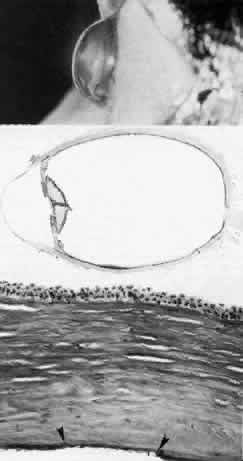

Sclerocornea

In sclerocornea (Fig. 4), the limbus is ill-defined since opaque scleral tissue with fine vascular conjunctival arcades extends into the peripheral cornea. A broad range of corneal involvement is possible, with the most extreme being complete sclerification of the cornea. Ninety percent of cases are bilateral, although generally asymmetric. Most cases are sporadic; there is no known heredity. Sclerocornea is nonprogressive and must be differentiated from interstitial inflammatory conditions and arcus juvenilis (congenital peripheral lipid deposition, also known as anterior embryotoxon). Sclerocornea is associated with cornea plana in approximately 80% of cases.44 Other associated ocular abnormalities include microphthalmos, iridocorneal synechiae, persistent pupillary membrane, dysgenesis of angle and iris, congenital glaucoma, colobomas, and posterior embryotoxon of the fellow eye.45 Somatic abnormalities sometimes occur along with associated chromosomal abnormalities; they include mental retardation, deafness, and craniofacial, digital and skin abnormalities.44

Fig. 4. Sclerocornea. Schematic drawing of ocular features Top left. In a minimally affected patient with additional findings of ptosis, strabismus, and hearing loss, only the peripheral cornea is opacified. Top center. In this advanced case with chromosomal translocation and multiple congenital abnormalities, the entire cornea is sclerified and the fine vascular arcades extend centrally from the conjunctiva and sclera. Top right. Light micrograph of anterior cornea shows edematous disorganization of epithelium, fragmentation of Bowman's membrane (B), and interstitial vascularization (V) (hematoxylin-eosin, × 200). Middle left. Transmission electron micrograph of normal human corneal stroma is shown for comparative purposes. Note uniform 240- to 260-nm collagen fibril diameter (× 50,000). Middle right. Transmission electron micrograph of sclerocornea at same magnification shows disorganized array of collagen fibrils that measure as much as three times normal diameter (× 50,000). Bottom. Transmission electron micrograph of posterior cornea shows abnormal Descemet's membrane of less than 1μm thickness (DM, bracketed) and attenuated endothelial cells (× 10,500). (Schematic. Grayson M: Diseases of the Cornea, p 32. St. Louis, CV Mosby, 1979; Top center and right. Rodrigues MM, Calhoun J, Weinreb S: Sclerocornea with an unbalanced translocation [17p, 10q]. Am J Ophthalmol 78:49, 1974)

Ultrastructural studies22,46,47 have shown the involved stroma to assume the morphologic features of scleral tissue, with irregularly arranged collagen fibrils of variable and immensely enlarged diameter for corneal tissue (up to 150 nm, comparable to normal scleral collagen). The precise lamellar organization of normal corneal stroma is not present; thus optical clarity is not achieved. Various abnormalities of endothelium and Descemet's membrane exist, from attenuation to focal absence. Descemet's membrane is generally thin, with multilaminar deposition of basement membrane-like collagen.

Pathophysiologically, sclerocornea may result from developmental arrest of limbal differentiation during neural crest migration, as occurs with the other mesenchymal dysgeneses.22